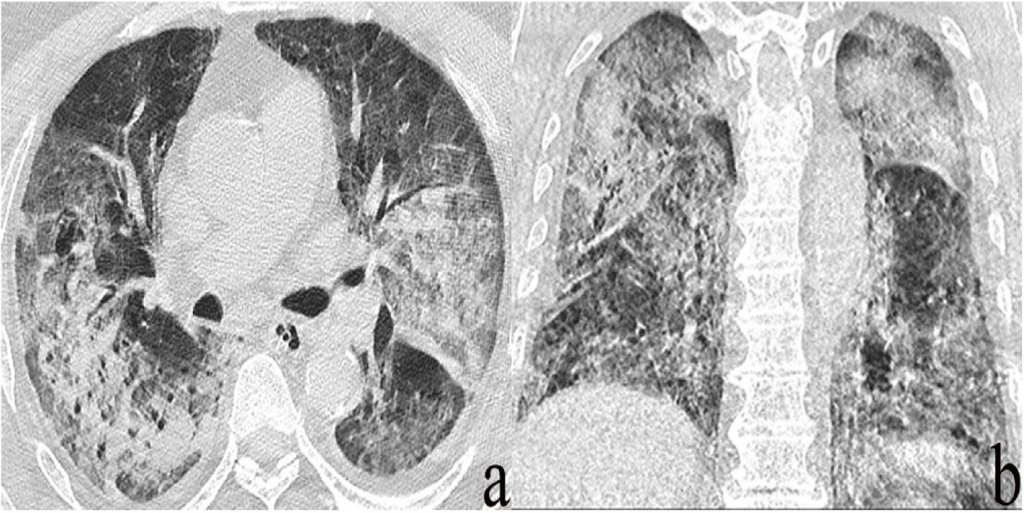

Typical HRCT scan of IPF patients. (a) Axial HRCT image acquired at the Can Hrct Detect Heart Disease Learn about 3 key parameters that impact interpretation of hrct, including slice thickness, reconstruction kernels or algorithms, and radiation. It appears to be just as. Identical findings can be seen in patients with lymphoma and in children with hiv infection, who develop lymphocytic interstitial. A cardiac ct scan is a noninvasive, painless test that evaluates the heart and surrounding blood. Can Hrct Detect Heart Disease.